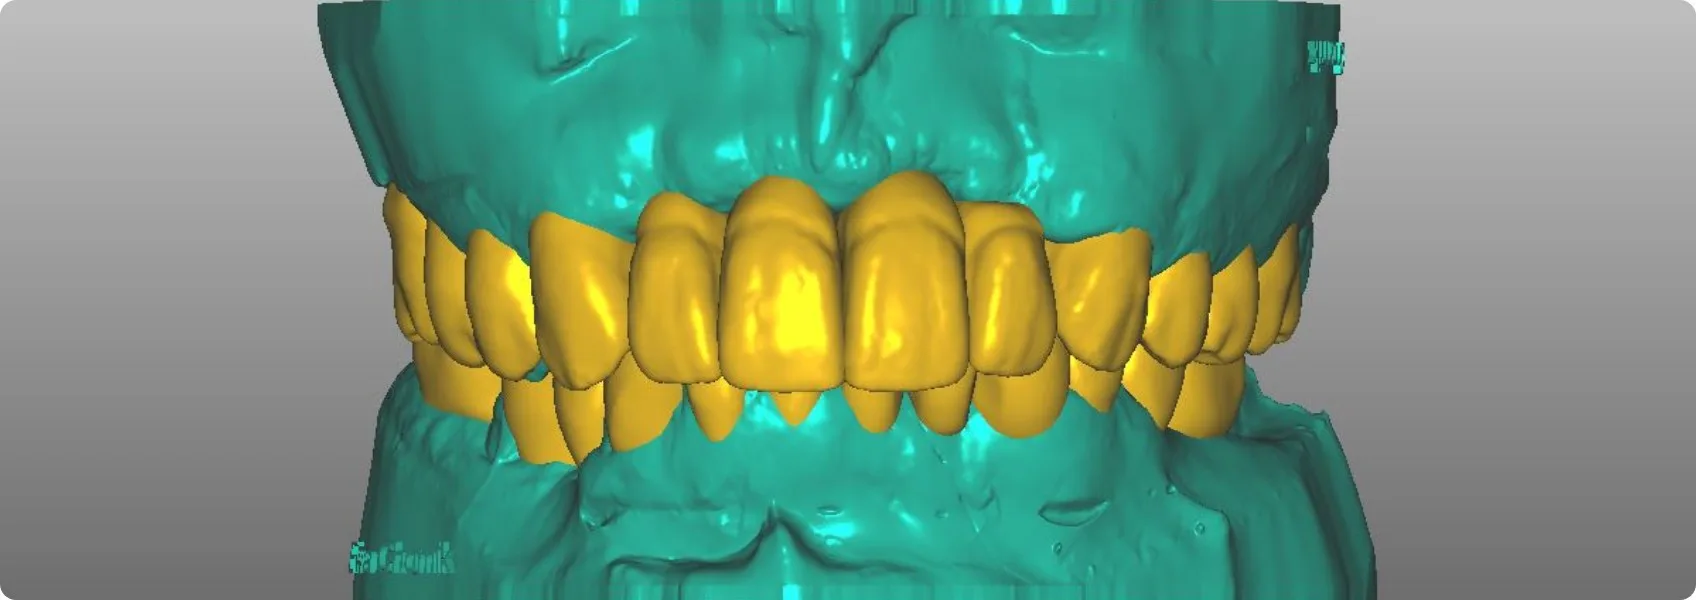

Dopiero wtedy możemy przejść do dalszych kroków. Technik dentystyczny drukuje model nowego zgryzu Pacjenta (tzw. wax-up), który będzie naszym wzorcem do dalszej pracy.

W NDC Pacjent aktywnie uczestniczy w projektowaniu swojego nowego uśmiechu. Zanim przystąpimy do jakichkolwiek nieodwracalnych działań na zębach, tworzymy wstępną wizualizację przyszłej odbudowy. Można ją założyć i przejrzeć się w lustrze!

Jest to tzw. mock-up, czyli tymczasowy model nowych zębów, który umieszczamy w ustach Pacjenta na jego własnych zębach, bez żadnej ingerencji w nie. Mock-up możemy po chwili ściągnąć.

To jak „przymiarka uśmiechu”. Pacjent na tym etapie może ocenić kształt, wielkość, a nawet funkcję przyszłej rekonstrukcji i zgłosić wszelkie uwagi. To bezcenny etap, który eliminuje ryzyko rozczarowań.